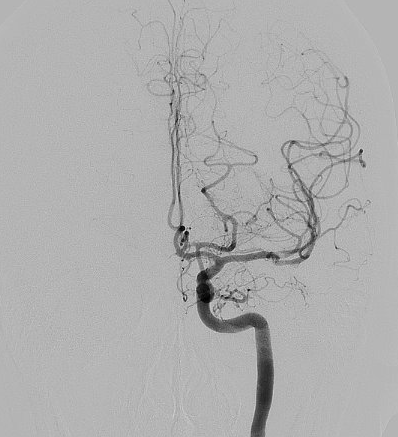

Angiografia cerebrale di controllo post-operatorio